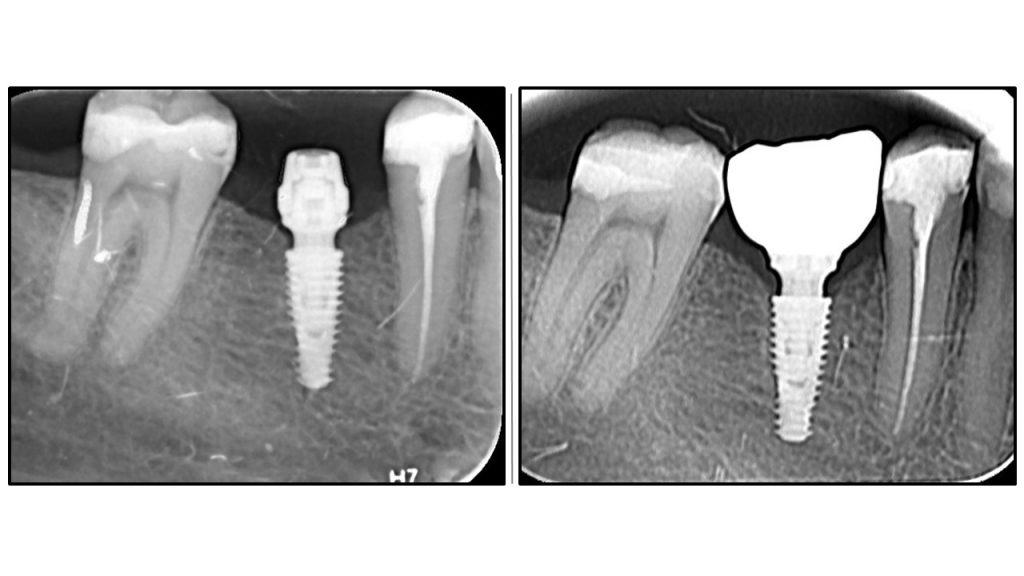

Radiographic Analysis: Crestal Bone Stability

Comparative radiographic study of crestal bone stability: OAOT protocol. Postoperative radiography vs. Final prosthetics.

The first image showing postoperative radiography and the second final ceramic crown

Bone remodelling

Bone remodelling around implant abutment connection is flawless

Stable peri implant tissue

No bone recession is visible

OAOT protocol - superior results.